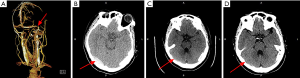

For early complications post-stenting, 4 patients (11.4%) in control group complicated with stenting-related subdural hematoma, all the hematomas located at the contralateral of the stenting side (Figures 1,2). Whereas, no subdural hematoma event (0.0%) occurred in perioperative management group, P=0.031. Other complications, such as stent-adjacent stenosis, intraluminal thrombosis, and intraluminal restenosis showed no statistic difference between the two groups.

Importance of strictly preoperative ICP control

In this study, 4 out of 35 patients in control group (11.4%) complicated with subdural hematoma, moreover, all of the hematomas located at the opposite side of the stent. However, no hematoma event occurred in the perioperative management group. The mechanism of the stenting-related contralateral side subdural hematoma was not clarified. A possible explanation for this phenomenon was that patients in the control group did not undergo a transiently strictly preoperative ICP reducing therapy. Therefore, we hypothesized that ICP on the stenting side was suddenly reduced after the stent self-expended, which resulted in a rapid pressure gradient of the ICP between two sides of the midline. The brain tissue on the opposite hemisphere may “drift” towards the stenting side to some degree. Whereby, a tear between the vessels in brain tissue and the dura mater resulted in a subdural hematoma. The same type of intracranial hemorrhage has also appeared on the side contralateral to the stenting in other studies (5,22). Our results suggest that patients with unilateral transverse sinus stenosis and severe IH may benefit from transiently strictly ICP control. However, this hypothesis still needs more evidence to prove.